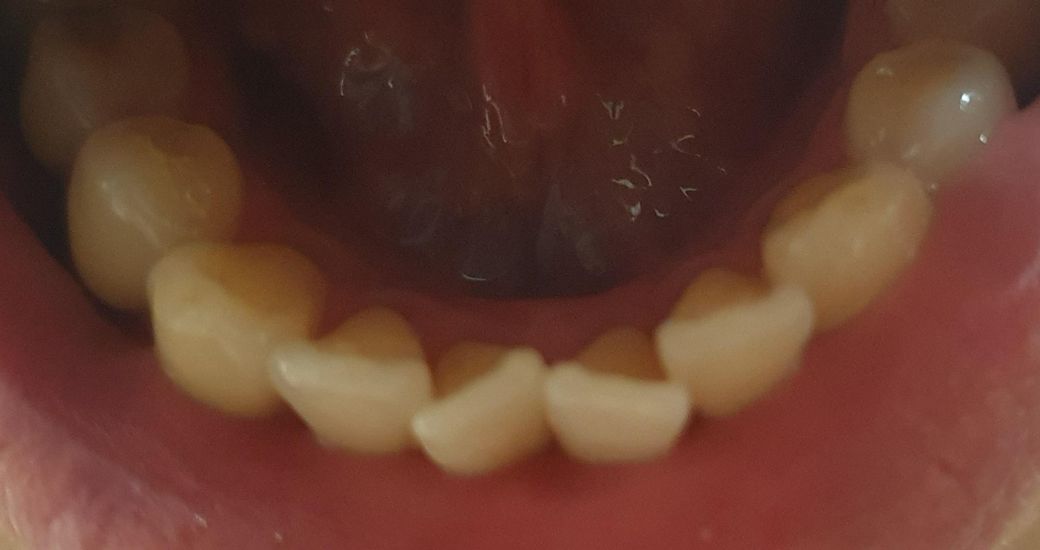

아래쪽 앞니 어긋나는데 교정 필요할까요?

중년 남성입니다. 아래쪽 앞니 두개가 언제부터인가 점점 바깥쪽으로 어긋나서 이른바 나비치아, V자형 치아가 되고 있는데, 교정이 필요할까요 아니면 그냥 놔둬도 될까요? 그냥 놔뒀을 때 계속 심해져서 치아가 빠지지는 않을까요?

사진 올렸으니 의견 부탁드립니다.

• 1번 째 사진